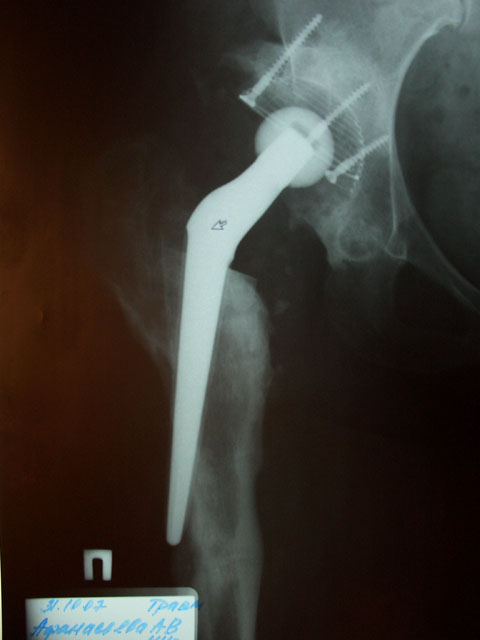

Прошу совета дальнейшей тактики лечения-нужна ли операция, и если нужна в

какие сроки. R-снимок в приложении.